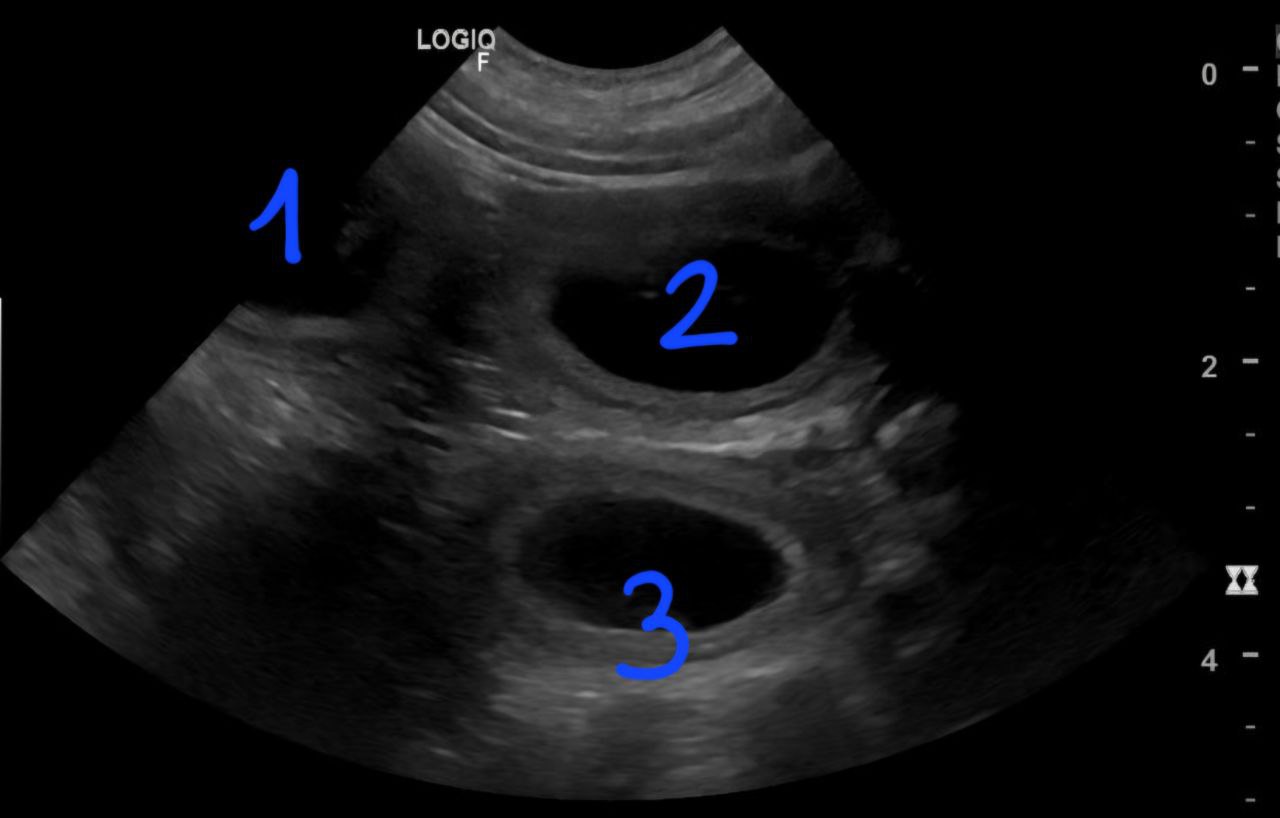

Am 10.12. hatten wir einen Ultraschall-Termin und die schon bereits vermutete Schwangerschaft wurde bestätigt.

Drei Fruchtblasen sind zu sehen.

Die Tierärztin konnte drei Welpen gleichzeitig im Ultraschall erkennen. Wie viele Welpen es aber genau sind, blieb bis zur Geburt eine Überraschung.